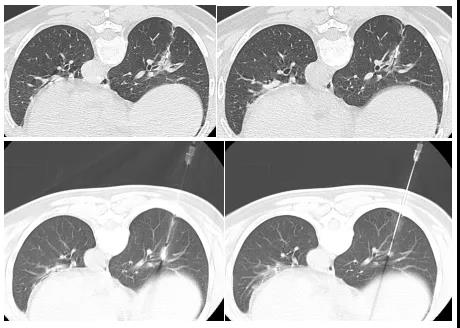

池嘉昌副教授:“GGO只是一块变质的肺组织,并不是实体肿瘤,我们从国外文献中看到一些学者使用针尖为圆形的套管针来进行穿刺,避开了重要的血管或组织。于是,我们就尝试用钝性圆头微波针进行了许多离体和活体实验,得出圆头微波针真的可以在肺部中穿透,也发现该微波针能穿过GGO,并且在碰到血管时也不会引起出血。这给了我们很大的信心。”

“以往对于周围有大血管(2mm)的GGO微波消融相对是比较危险的,有了新的微波针,我们就能把微波消融的使用遍布到整个肺叶,哪怕是贴近心脏或肺动脉主干的危险位置,都能做到穿刺和消融的目的。”

一61岁女性患者,于2018年底因体检胸部CT发现双肺GGO,2019年2月遂于仁济医院胸外科行胸腔镜下左肺上叶舌段切除术,术后病理提示原位腺癌。

2019年5月复查胸部CT提示左肺近肺门部GGO,最大径约10mm,提示病情复发。此时,患者因考虑再次手术可能要切术肺叶而不愿意再次手术,经医生团队讨论,遂行微波消融治疗。该患者在消融后即刻行穿刺活检,病理显示为原位腺癌。在2020年的术后1年复查中,患者肺部的消融灶吸收良好。